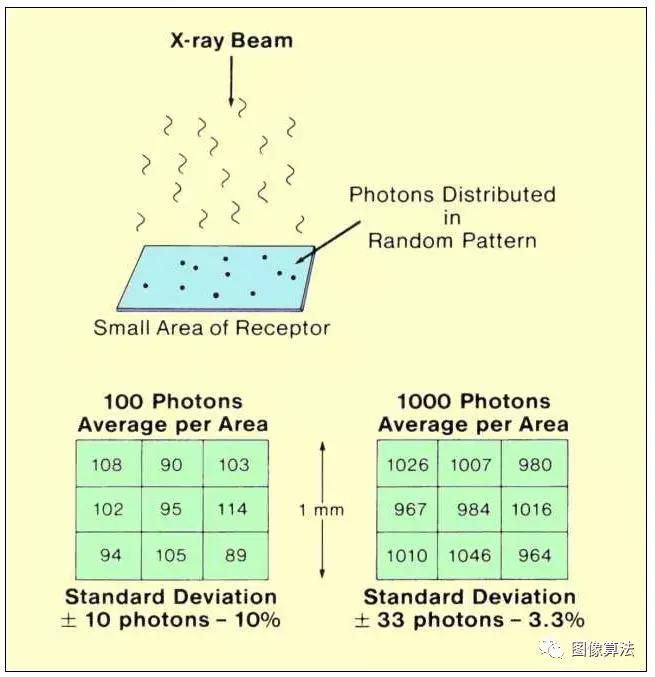

让我们使用下面的插图来更新我们的辐射量子特性的概念,看看它是如何产生图像噪声的。在这里,我们看到X射线束的一部分形成了图像中一个小区域的曝光。请记住,X射线束是一个单独的光子阵列。因为光子是独立的,所以它们随机分布在图像区域内,有点像落在地面上的前几滴雨。在某些点上可能存在多个光子(液滴)的簇,以及仅收集少量光子的区域。这种不均匀的光子分布在图像中显示为噪声。的 噪声的量是由所确定的 在光子浓度变化由点到一个小的图像区域内指向。

量子噪声的概念

幸运的是,我们可以在某种程度上控制光子波动和产生的图像噪声。上图显示了两个1毫米的方形图像区域,细分为九个较小的方形区域。两个区域之间的差异是落在该区域内的光子浓度(辐射暴露)。第一个平均每个小方块有100个光子,第二个平均每个小方块有1000个光子。对于典型的诊断X射线束,这相当于分别约3.6μR和36μR的受体暴露。请注意,在第一个大区域中,没有一个较小的区域恰好有100个光子。在这种情况下,每个区域的光子数范围从低89光子到高114光子。但是,我们不会 使用这两个极值来衡量光子波动。因为大多数小区域的光子浓度更接近平均值,所以更适合用标准偏差表示光子变化。标准偏差是统计分析中常用的数量(参见标题为“统计”)表示数量之间的差异或变化量。标准偏差的值有点像小区域中的“平均”偏差量或变化量。光子分布的特征之一是波动量(标准偏差值)与平均光子浓度或曝光水平有关。每个区域的平均光子数的平方根提供了对标准偏差值的近似估计。在该示例中,标准偏差具有每面积10个光子的值。由于这是平均值的10%,因此该曝光下的量子噪声(光子波动)具有10%的值。

现在让我们考虑右边的图像区域,每个区域平均接收1000个光子。在这个例子中,我们还发现没有一个小区域正好接收到1000个光子。在这种情况下,光子浓度范围从每个区域964个光子到1,046个光子。取平均光子浓度的平方根(1,000)得到33.3光子的标准偏差值。看起来我们的光子波动或噪声比其他区域更高。然而,当我们将标准偏差表示为平均光子浓度的百分比时,我们发现噪声水平实际上已降至3.3%。

我们刚刚观察到量子噪声可能是最重要的特征; 可以通过增加用于形成图像的光子浓度(即曝光)来减少它。更具体地,量子噪声与暴露于受体的平方根成反比。